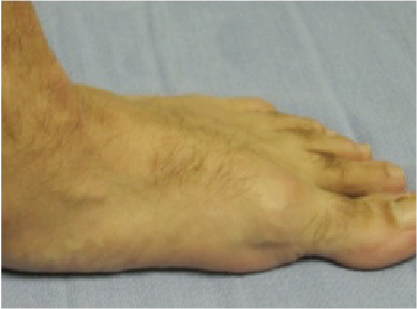

Patients with stage 2 PTTD present with a variety of deformities depending on planal dominance of the deformity. In patients with an unstable naviculocuneiform joint, one may note a sagittal plane collapse with a medial column sag demonstrating a naviculocuneiform fault radiographically. In transverse planal dominant deformities, one will see the too many toes sign with abduction of the midfoot and forefoot. The frontal plane deformities have a moderate heel valgus presentation with a forefoot supinatus or varus condition. The inability to perform a single limb rise test without inversion of the heel is common for advanced deformities where the function of the posterior tibial tendon has been lost due to an attenuated or ruptured posterior tibial tendon.

The performance of Jack’s test will help reveal the reducibility of the flatfoot deformity.6 A test I commonly perform on my patients involves external rotation of the leg with maintenance of lateral column weightbearing while I find the midtarsal joint neutral position. I have the patient hold his or her foot in this position, and evaluate the forefoot position. If I can manually reduce the deformity to weightbearing on the first ray, I consider this forefoot supinatus, which will reduce once I have addressed the proximal deformity by improving the lever of the peroneus longus tendon. If I cannot manually reduce the forefoot deformity, it is a forefoot varus that requires surgical correction with a Lapidus procedure, Cotton osteotomy, or wedging the naviculocuneiform arthrodesis. It is important to assess the difference between forefoot supinatus and forefoot varus.